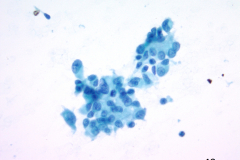

Specimen Type: FNA of RUL nodule. ThinPrep® Non-Gyn and conventional smears with Diff Quik stain, H&E stain (traditional cell block), Papanicolaou stain and AE1/AE3 (traditional cell block).

Cytology: Cytologically epithelioid sarcoma presents as numerous dispersed round, polygonal or spindle-shaped cells. Nuclei are large, vesicular, and eccentrically placed with small nucleoli. The nuclei can be single or multiple and pleomorphism may be present. The predominant arrangement is single cells, but they can also be arranged in sheets and loose cohesive clusters with fibrillary matrix. The cytoplasm is dense, may have small vacuoles with distinct cell borders. A background of necrosis is not uncommon.1-3